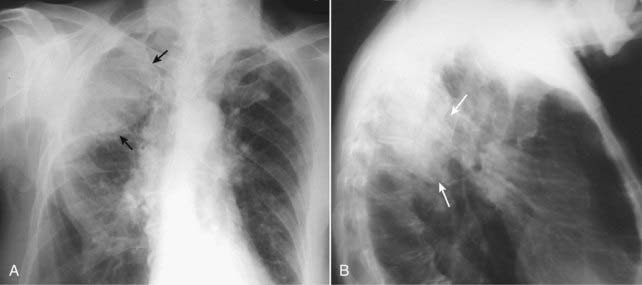

Figure 6-1 Dressler syndrome (postpericardiotomy/postmyocardial infarction syndrome).

A left pleural effusion (A) is present (solid black arrows). This syndrome typically occurs 2 to 3 weeks after a transmural myocardial infarct. It also can occur following pericardiotomy such as occurs in patients undergoing coronary artery bypass surgery, as in this case. The combination of chest pain and fever, left pleural effusion, patchy left lower lobe airspace disease, and pericardial effusion several weeks following a myocardial infarction or open-heart surgery should suggest the syndrome. It usually responds to high-dose aspirin or steroids. This patient has a dual lead pacemaker in place and, on the lateral projection (B), the leads are seen in the region of the right atrium (dotted black arrow) and right ventricle (arrowhead).